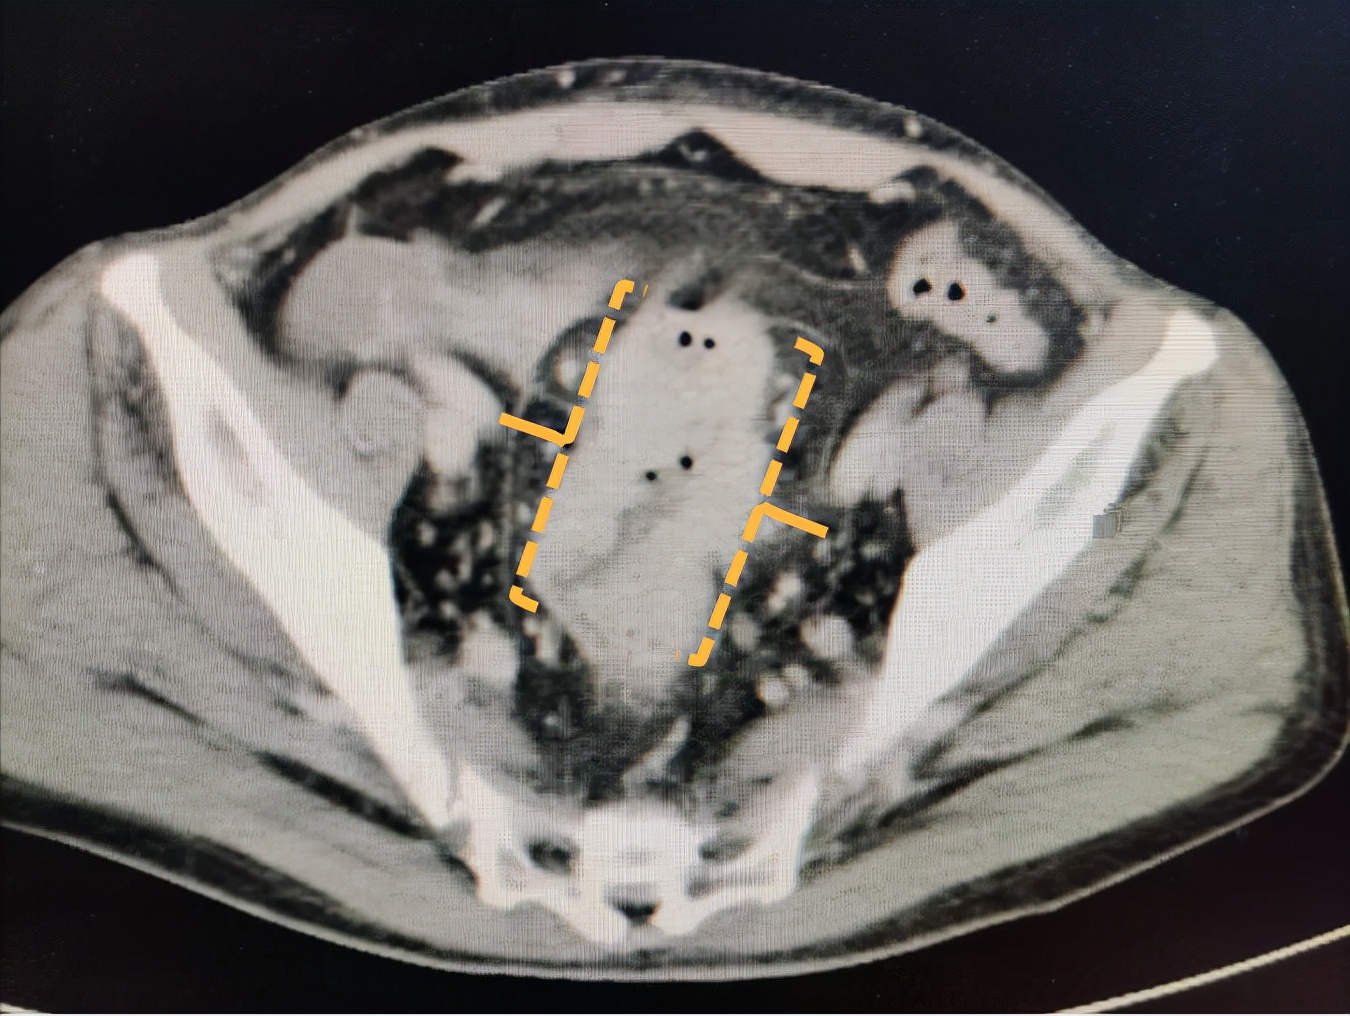

当我看了病史,在工作电脑上看到了这样的影像资料时(如下图),我宁可认为自己看错了。因为这是明确的、典型的大肠癌的影像学表现。一个最让人痛心的结果。

乙状结肠-直肠交界处明显增厚,肠腔狭窄,周围有些较大淋巴结

大致的测量了范围,厚约2cm,长度约7cm